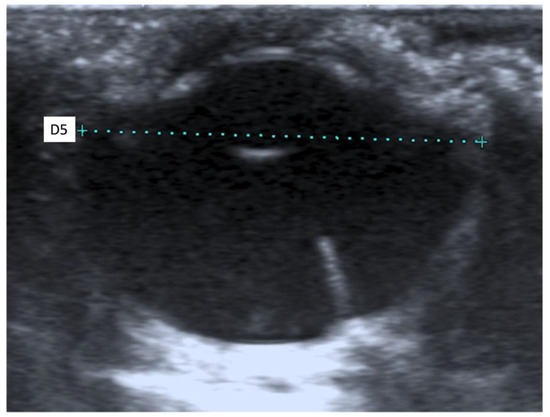

3.2. Ultrasound Biometric Measurements

| (a) | |||||||||||||||

| Both breeds | OS 1 (n 3 = 27) | OD 2 (n 3 = 27) | Mean OS 1 + Mean OD 2 | ||||||||||||

| D1 5 | D2 6 | D3 7 | D4 8 | D5 9 | D1 5 | D2 6 | D3 7 | D4 8 | D5 9 | D1 5 | D2 6 | D3 7 | D4 8 | D5 9 | |

| Mean (mm) | 1.68 | 7.41 | 4.29 | 15.09 | 18.01 | 1.66 | 7.48 | 4.32 | 15.16 | 18.07 | 1.67 | 7.44 | 4.30 | 15.12 | 18.04 |

| SD 4 (mm) | 0.16 | 0.18 | 0.11 | 0.44 | 0.49 | 0.16 | 0.20 | 0.17 | 0.37 | 0.49 | 0.12 | 0.17 | 0.12 | 0.37 | 0.43 |

| Median (mm) | 1.70 | 7.40 | 4.30 | 15.20 | 18.10 | 1.70 | 7.50 | 4.30 | 15.20 | 18.00 | 1.65 | 7.45 | 4.30 | 15.05 | 18.05 |

| Maximum (mm) | 2.10 | 7.70 | 4.50 | 15.80 | 18.80 | 1.90 | 7.80 | 4.70 | 15.90 | 18.90 | 1.95 | 7.75 | 4.55 | 15.80 | 18.85 |

| Minimum (mm) | 1.40 | 7.00 | 4.10 | 14.30 | 16.80 | 1.30 | 7.10 | 4.10 | 14.60 | 17.30 | 1.45 | 7.05 | 4.10 | 14.50 | 17.25 |